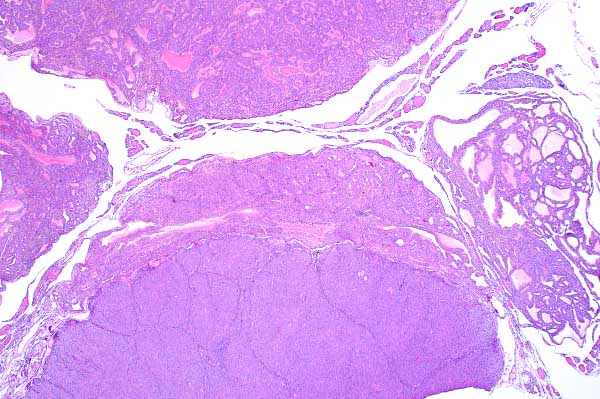

2x   |   Hematoxylin and Eosin

Lobules are separated by a moderate amount of fibrous connective tissue.